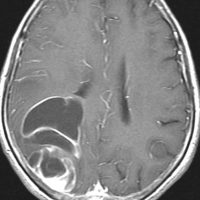

グリオマトーシス gliomatosisのような例

病理組織診断で退形成性星細胞腫 WHO grade IIIとされるものに,全く違った性質を示すグリオーマがあります。

ゆっくり進行する軽い右麻痺で発症した50歳くらいの患者さんです。脳梗塞や脱髄疾患を疑われていました。左頭頂部皮質下から脳梁,内包,中脳大脳脚まで非常に広範囲に浸潤しています。single cell infiltrationという浸潤形態を想像させます。右下はT!ガドリニウム造影で,この部分だけが増強所見があります。

おそらく今後は,diffuse hemispheric glioma WHO grade 4と診断されます。

軽度の異型性を認め,細胞密度が高く核分裂が目立ち,Ki-67 (MIB)染色率は20%に達しました。1p/19q欠失はなくMGMTメチレーションもありませんでした。IDH変異は調べていない年代の例で不明です。病理組織診断でanaplastic astrocytomaとされました。治療は,全脳に近い照射野となるので50Gy/25分割が限界でした。TMZを併用しています。

照射後も症状は一度も改善することなく悪化して,数ヶ月後にはもともと腫瘍が見えなかった内側側頭葉に大きな腫瘍塊が発生増大しました。この例は退形成性星細胞腫と診断するしかなかったものですが,2020年時点でははっきり分類できない星細胞系腫瘍です。